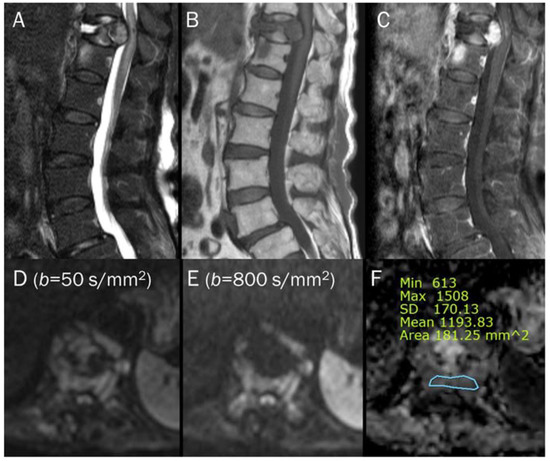

7.4. Vertebral Endplate Changes